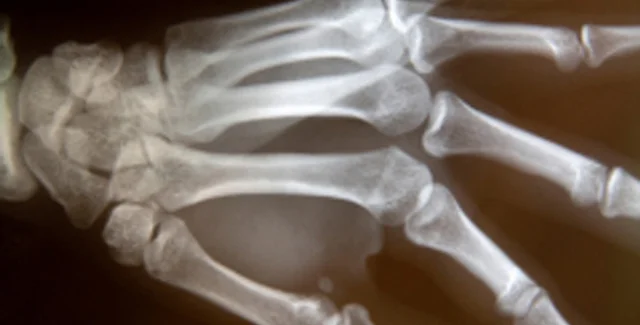

На первое место британцы поместили открытие рентгеновского излучения и изобретение использующих его медицинских приборов. Этот вариант поддержали 10 тысяч опрошенных. Второе место заняло открытие пенициллина. На третье место жители Великобритании поместили определение структуры ДНК. Далее следуют создание корабля "Аполлон-10" и баллистической ракеты "Фау-2", изобретение паровоза, вычислительных машин, парового двигателя, массового автомобиля и телеграфа. Исходный список изобретений был составлен сотрудниками Музея науки.